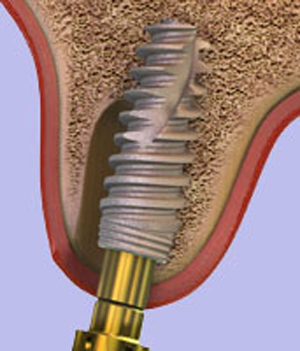

Een tandheelkundig implantaat is in wezen een titaniumschroef of -cilinder, tussen 4 mm en 16 mm lang, die wordt ingebracht in een voorbereide holte in de kaak en fungeert als een vervangende wortel voor de ontbrekende tand of kies. Een speciale bevestiging, het abutment genaamd, wordt aan de bovenkant van het implantaat bevestigd en vormt de externe verbinding met de vervangende tand (kroon). Er zijn ook implantaten uit één stuk waarbij het abutment en het implantaat deel uitmaken van één stuk.

- Inbrengen van het implantaat: implantaatchirurgie kan in één of twee fasen worden uitgevoerd, afhankelijk van de individuele omstandigheden. In beide gevallen omvat de operatie het maken van een kleine incisie in het tandvlees om het bot bloot te leggen en vervolgens met behulp van speciale boren om het “implantaat bed” voor te bereiden waarin de implantaten worden ingebracht. Een operatie in twee fasen kan nodig zijn als het nodig is om de hoeveelheid bot op de implantatieplaats te vergroten door gebruik te maken van een botopbouw of een techniek om bot te regenereren.

Het schroefdeel van het implantaat moet volledig in het kaakbot geplaatst worden en in geslonken kaken kan dat niet altijd. De kaak is dan vaak aan de wangzijde te smal geworden waardoor het implantaat daar niet volledig bedekt is met bot. Mocht de kaakwal in de breedte of de hoogte tekort komen wegens deze dimensionale veranderingen dan zal een botherstel operatie worden uitgevoerd om dit op te lossen (Guided Bone Regeneration) . Deze operatie kan vaak tegelijkertijd met het plaatsen van het implantaat worden uitgevoerd.